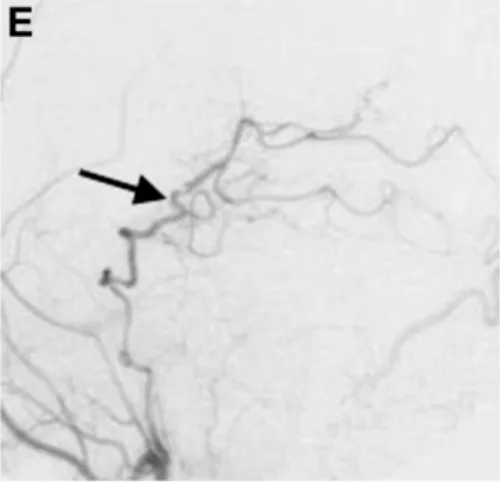

手术过程顺利,未发生术中并发症。术后一周颈外动脉血管造影显示,经新建分流血管,左侧大脑后动脉供血区血流完全通畅(图E箭头标注),未见缺血征象。

术后一周颈外动脉血管造影显示,经分流血管,整个左侧大脑后动脉供血区血流良好(箭头标注)。